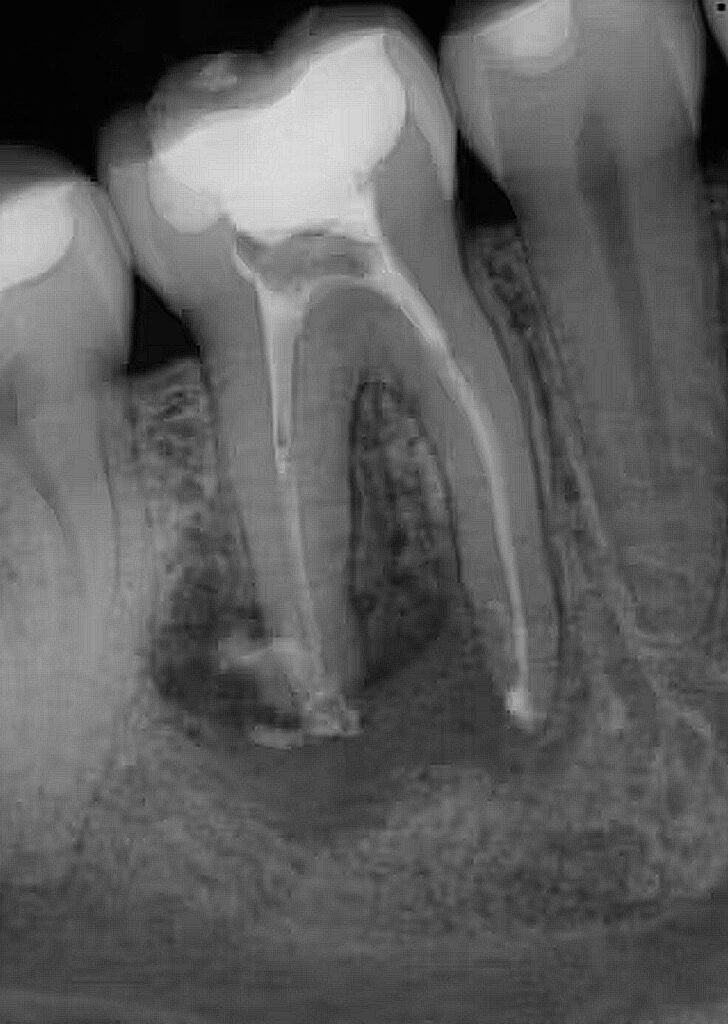

- Failed Root Canals: Root canals have a success rate over 90%. However, if a re-treatment or surgical intervention fails, extraction is the final step to eliminate infection. (Rao S et al. (May 10, 2023) Incidence of Endodontic Failure Cases in the Department of Conservative Dentistry and Endodontics, DY Patil School of Dentistry, Navi Mumbai. Cureus 15(5): e38841. doi:10.7759/cureus.38841)

Standard 2D X-rays can hide curved roots or extra canals. At Finesse Dentistry, we use 3D CBCT Scans to see your tooth from every angle before we even touch an instrument. This technology allows us to:

- Evaluate every tooth in 360 degrees to see what can be saved versus what is truly beyond repair.

- Plan the exact path of removal and protect essential anatomy like nerves and sinuses.

- Section molar roots into smaller parts for a quicker, less traumatic “divide and conquer” exit.